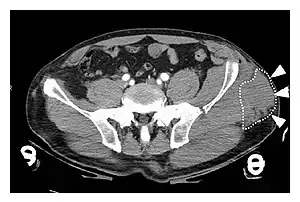

| A Morel-Lavallée lesion is a closed traumatic soft-tissue degloving injury, caused by separation of the hypodermis from the underlying fascia.[1] It most frequently occurs in the peritrochanteric region along the proximal lateral thigh,[1] such as in this CT scan. |